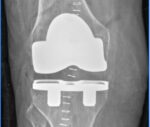

September 2024: Robotic Total Knee Arthroplasty in a young patient with poliomyelitis and multilevel extra-articular deformities – achieving a well-balanced knee without increasing joint constraint: Dr Rajeev K Sharma & Dr Udit Vinayak